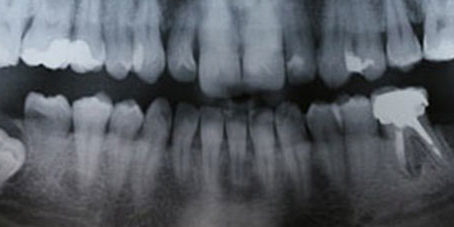

Las muelas del juicio son cuatro y son los últimos molares en aparecer o erupcionar, ubicándose en la zona posterior de cada arco dentario. Se cree que estos dientes eran necesarios en épocas remotas cuando el ser humano tenía una alimentación en base a alimentos crudos, pero en la actualidad, la boca no cuenta con suficiente espacio para albergarlas, por lo que su extracción es lo más recomendado.

Sin embargo, pueden ocurrir diversas situaciones con las muelas del juicio, la primera, que éstas no aparezcan durante toda la vida; segundo, que no se genere ninguna molestia al erupcionar los cordales o, tercero, que adopten una posición anómala, lo que implicará que las muelas afectadas queden retenidas total o parcialmente dentro del hueso o francamente impactadas contra los segundos molares, situación que requiere de intervención médica.

Es recomendable que a partir de los 18 años se acuda al dentista para una evaluación respecto a las muelas del juicio, para saber cómo está su desarrollo y si será o no necesario extraerlas. El especialista determinará cuando y de qué manera deberán removerse estos molares, generalmente se trata de un procedimiento de intervención quirúrgica que no debería conllevar mayores dificultades.